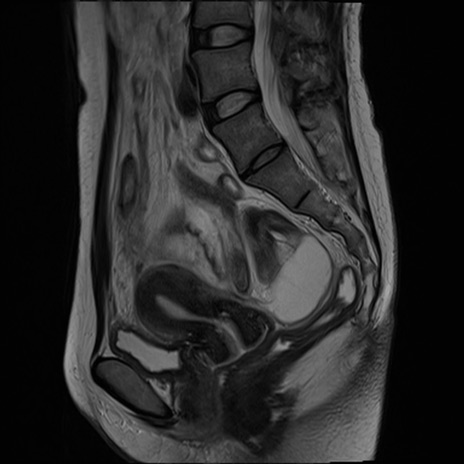

症例39 T2WI(矢状断像)

MRI(4日後)